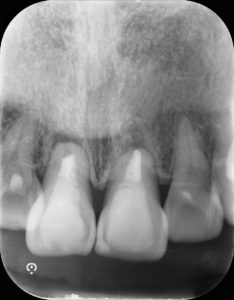

治療中

マイクロスープ下にて古い充填物を除去すると根管内は汚染物質が多量存在したため、汚染物質の除去を徹底的に行い次亜塩素酸ナトリウムで殺菌を行った。

根管内の清掃を終えた後根管充填を行った。